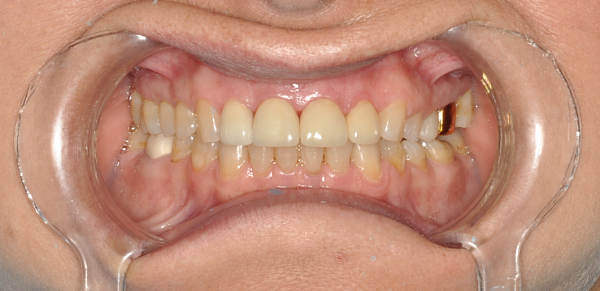

Пациент, 54 года. Замена старых металлических протезов на диоксид циркония.